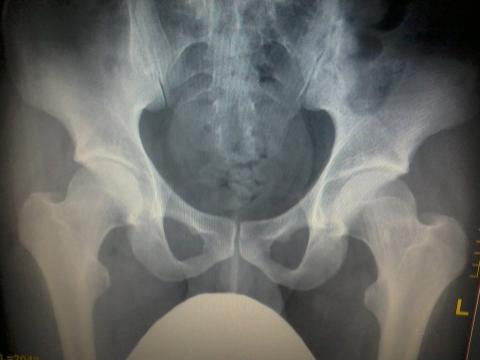

Pro větší náhled klikněte na obrázek

Dobrý deň, mám s touto stránkou celkom dobré skúsenosti, tak preto sa na vás obraciam znova. Mám taký problém, že ma už asi tretí deň tupou bolesťou občas pobolieva ľavý bedrový kĺb. Pričinil som si to sám - stalo sa mi to pri sexe,proste nejak som dostal nohu do neprirodzenej polohy, aj som citil že to nieje ono ale vydržal som...A potom ma začali bolieť obe kĺby. Pravý sa upokojil a ľavý bolí stále. Je to tupá bolesť-len pri dlhšej chôdzi občas prejde do ostrejšej a musím na pár sekúnd zastať. Tupú bolesť pociťujem aj keď sedím, či ležím. Po schodoch lietam bez problémov..Ortopéd sa vyjadril že to mám len natihnuté z toho neprirodzeného pohybu. No moc tomu neverím. 4.8.2014 mi začína základný vojenský výcvik...chcel by s byť dovtedy v pohode...predpísal mi Aflamil alebo tak nejak...co mi teda moze byt? prejde to?dakujem za odpoved!

Dobrý deň, nie som ortopéd, ale internista, preto nemožem hodnotiť RTG snímok. Každopádne, ak ste nemal úraz typu pádu alebo nárazu, len ste mal nohy v neprirodzenej polohe, nemal by ste mať žiadnu zlomeninu. Pravdepodobne ste si natiahol sval, na bedrový klb sa upína veľa svalov, ktoré sa nachádzajú na stehne. Na RTG snímku nie sú vidieť makké tkanivá typu šlachy, svaly, vazy, viditeľné sú iba kosti a sčasti kĺby, ktoré sa dajú hodnotiť. Bohužiaľ, natiahnutý sval kdekoľvek na tele sa hojí dlho - třeba dodržať kľudový režim, nešportovať, oblasť klbu mazať Ibalgin gelom alebo inou protizápalovou masťou. Do augusta by ste mal byť v poriadku, ale naozaj je doležitý kľudový režim.